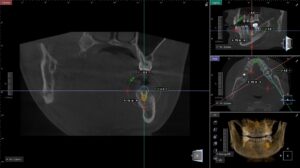

現在はCT撮影により、顎の骨を立体的に把握できます。

さらに、

・3Dデジタルシミュレーション

・コンピューター上での埋入位置設計

・サージカルガイドの作製

を行い、事前に完成形を設計してから手術を行います。

① 診断から埋入まで一貫したデジタル設計

CTデータをもとに、

埋入位置・角度・深さを事前にシミュレーション。

設計データをそのままガイドに反映するため、

誤差を最小限に抑えた治療が可能です。